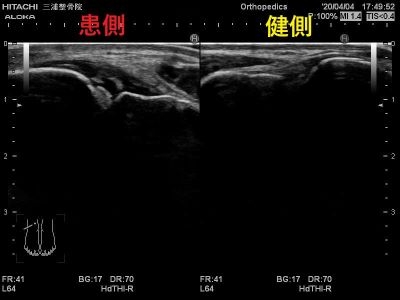

エコーではこのように写ります。

患側では大きく腫れて

正常な靭帯線維が見えないため

二分靭帯が断裂しています。